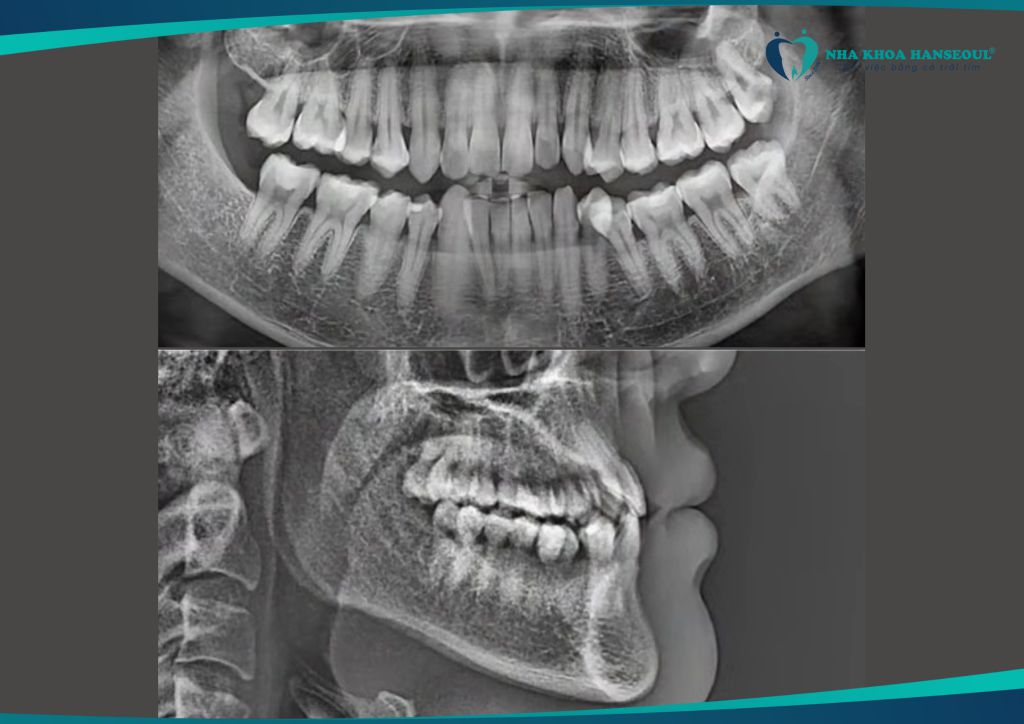

Anh Trường gặp phải tình trạng khớp cắn ngược hạng III móm. Đây là một dạng sai khớp cắn khiến hàm dưới đưa ra trước. Ảnh hưởng đến cả chức năng ăn nhai lẫn thẩm mỹ khuôn mặt. Ngoài ra, anh còn gặp tình trạng răng khôn sâu, thường xuyên đau nhức. Ảnh hưởng lớn đến sinh hoạt hằng ngày.

Anh Trường đến với Nha khoa Hanseoul và được bác sĩ chuyên môn thăm khám, tư vấn kỹ lưỡng. Anh quyết định nhổ răng khôn, tiến hành niềng răng trong suốt Invisalign để cải thiện toàn diện tình trạng răng miệng.